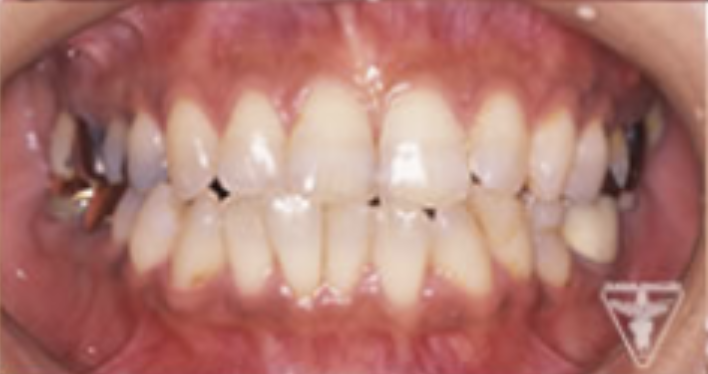

治療前

初診時の正面観・側方観・かみ合わせの面の状態を示します。

下の顎のずれがあるのを確認して下さい。